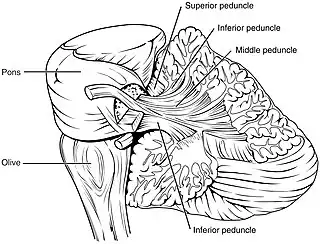

Sección coronal del cerebelo. Arbor vitae y pedúnculos cerebelosos.

Arbor vitae y pedúnculos cerebelosos.